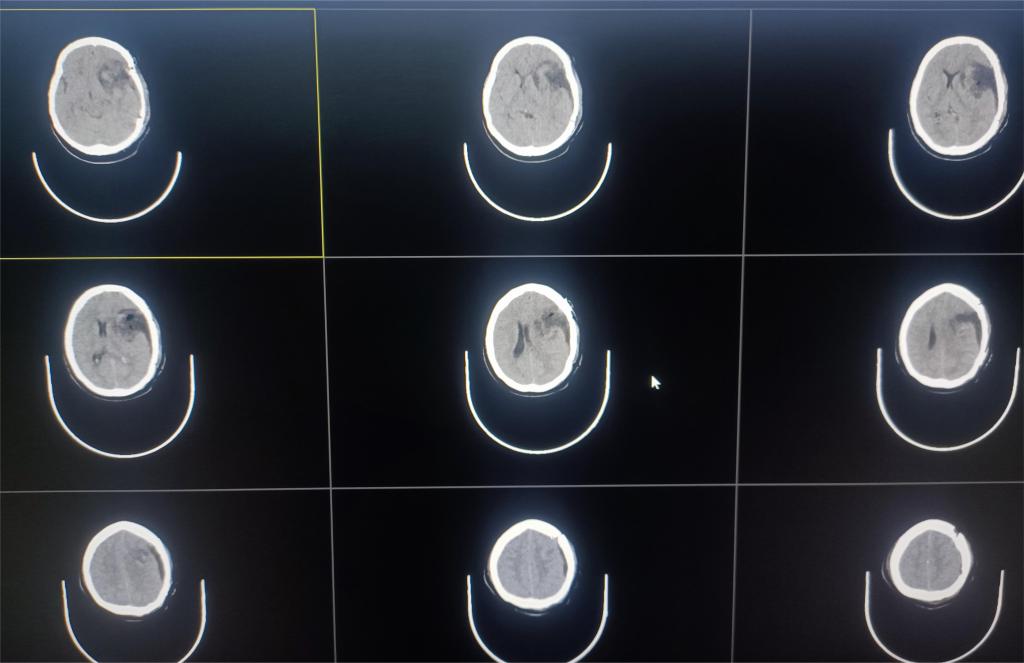

患者刘某,因“间断嘴角抽搐2周”到市中心医院就诊。行头颅磁共振提示:左侧额颞叶巨大脑膜瘤(图一)。

图一